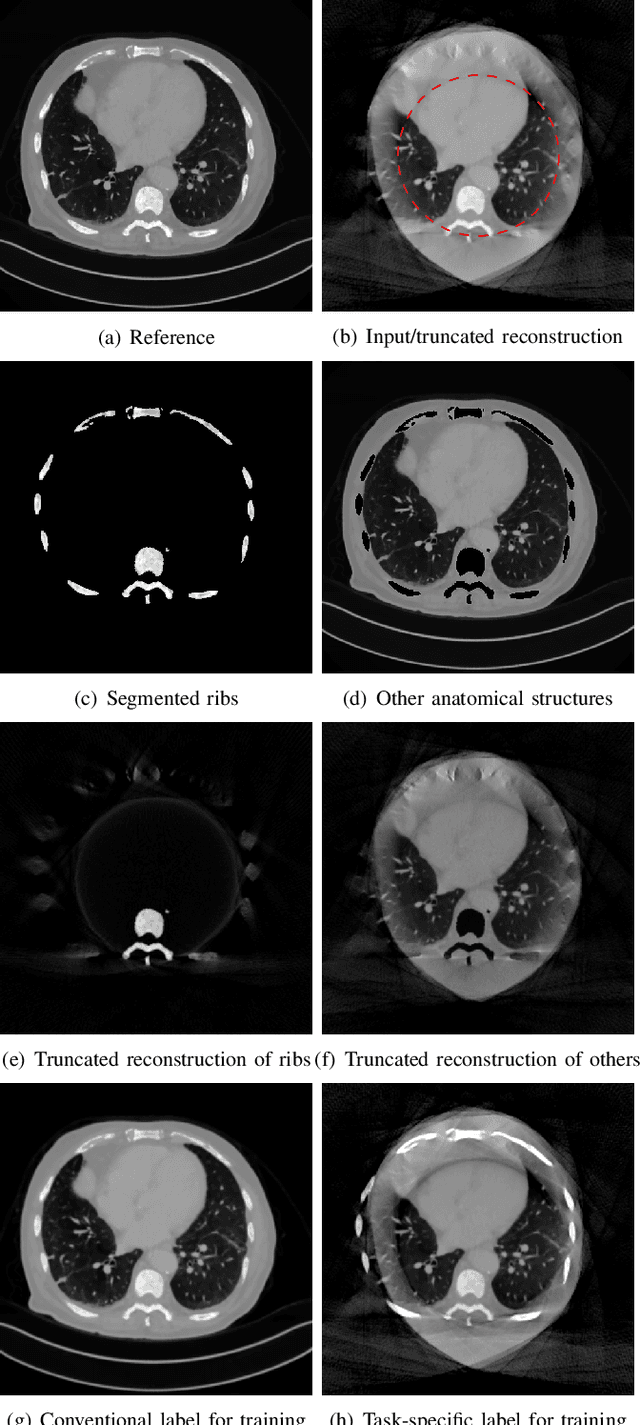

Abstract:Cone-beam computed tomography (CBCT) is widely used in interventional surgeries and radiation oncology. Due to the limited size of flat-panel detectors, anatomical structures might be missing outside the limited field-of-view (FOV), which restricts the clinical applications of CBCT systems. Recently, deep learning methods have been proposed to extend the FOV for multi-slice CT systems. However, in mobile CBCT system with a smaller FOV size, projection data is severely truncated and it is challenging for a network to restore all missing structures outside the FOV. In some applications, only certain structures outside the FOV are of interest, e.g., ribs in needle path planning for liver/lung cancer diagnosis. Therefore, a task-specific data preparation method is proposed in this work, which automatically let the network focus on structures of interest instead of all the structures. Our preliminary experiment shows that Pix2pixGAN with a conventional training has the risk to reconstruct false positive and false negative rib structures from severely truncated CBCT data, whereas Pix2pixGAN with the proposed task-specific training can reconstruct all the ribs reliably. The proposed method is promising to empower CBCT with more clinical applications.